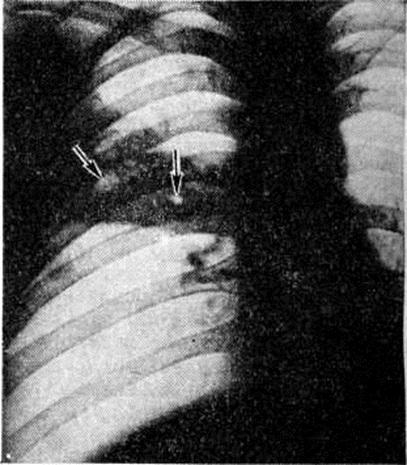

При пневмококковой Пневмония, в частности при её наиболее тяжёлом варианте — крупозной Пневмония, процесс начинается с развития небольшого очага серозного воспаления, располагающегося обычно в задних или в заднебоковых отделах лёгких, где содержатся пневмококки (рисунок 2, а). Патологический процесс распространяется прежде всего контактным путём и очень быстро захватывает значительную часть лёгкого — целую долю и даже несколько долей. Макроскопически лёгкое увеличено в объёме, его ткань резко отёчна и полнокровна. Эти изменения носят название стадии прилива.

В дальнейшем в экссудате нарастает количество нейтрофильных лейкоцитов, нередко одновременно с фибрином серозно-гнойный экссудат постепенно заполняет просветы альвеол (рисунок 2,6); последние достигают при этом размеров, которые они имеют на вдохе; пневмококки в это время фагоцитируются лейкоцитами и исчезают. При прогрессировании болезни более выраженные нарушения определяются на границе с неизменённой тканью органа. На разрезе лёгкое серого цвета с мелкозернистой или гладкой поверхностью, по консистенции напоминает печень (серая гепатизация лёгкого). У больных с повышенной проницаемостью сосудов к экссудату присоединяется большое количество эритроцитов, в результате чего лёгкое приобретает серо-красный или темно-красный цвет (красная гепатизация лёгкого).

В период выздоровления происходит рассасывание выпота; макроскопически в этот период лёгкие характеризуются пониженной воздушностью и эластичностью.

При очаговой пневмококковой Пневмония отмечаются сходные изменения, но с меньшей степенью выраженности.